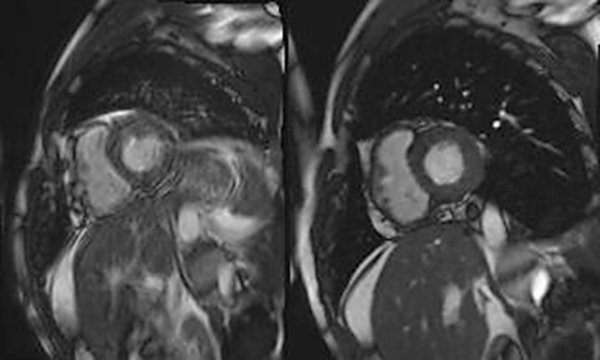

Abbildung 1: Produkt: MRT-Scan Vertrieb: Siemens Healthcare Segmentiertes Cardiac Cine (links: Aufnahmedauer 8 Herzschläge) im Vergleich mit einer Echtzeitaufnahme mit Compressed Sensing Cardiac Cine (rechts: Aufnahmedauer 1 Herzschlag). Bei einem Probanden mit Schwierigkeiten, den Atem anzuhalten (Dyspnoe) zeigt das segmentierte Cine verschwommene Bilder, während die Bildqualität bei Compressed Sensing Cardiac Cine nicht beeinträchtigt ist. © Siemens. Bildquelle: www.siemens.com/presse |

Vertrieb: Siemens Healthcare Segmentiertes Cardiac Cine (links: Aufnahmedauer 8 Herzschläge) im Vergleich mit einer Echtzeitaufnahme mit Compressed Sensing Cardiac Cine (rechts: Aufnahmedauer 1 Herzschlag). Bei einem Probanden mit Schwierigkeiten, den Atem anzuhalten (Dyspnoe) zeigt das segmentierte Cine verschwommene Bilder, während die Bildqualität bei Compressed Sensing Cardiac Cine nicht beeinträchtigt ist. © Siemens. Bildquelle: www.siemens.com/presse |